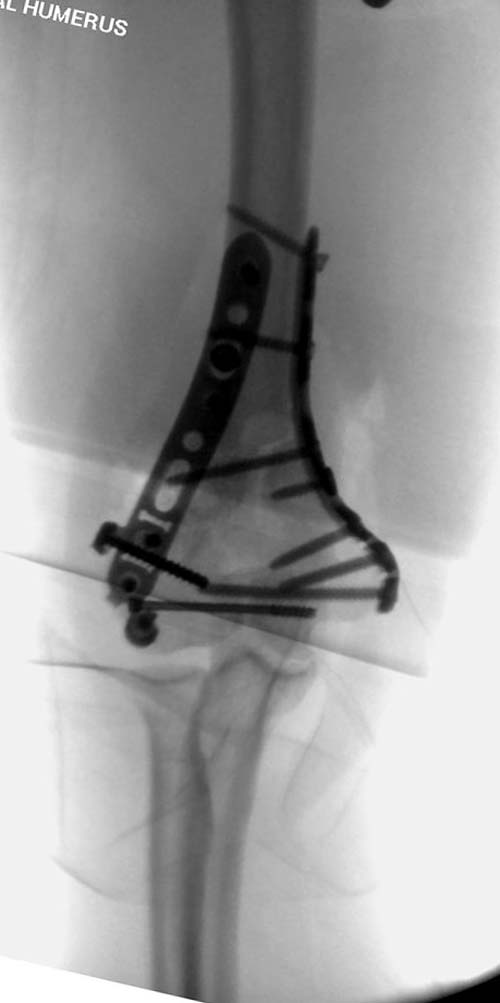

Здесь открытый перелом, временный наружный фиксатор и окончательная фиксация пластинами. Второй случай фиксация без остеотомии отростка пластинами Biomet-DePuy...